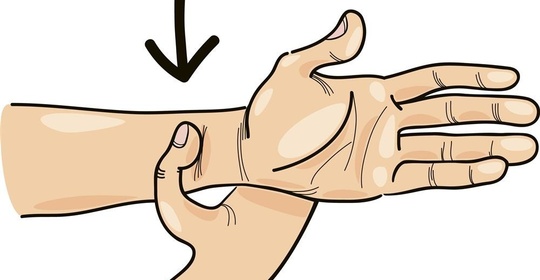

前臂旋轉痛:不同病症導致的頭痛與手部不適